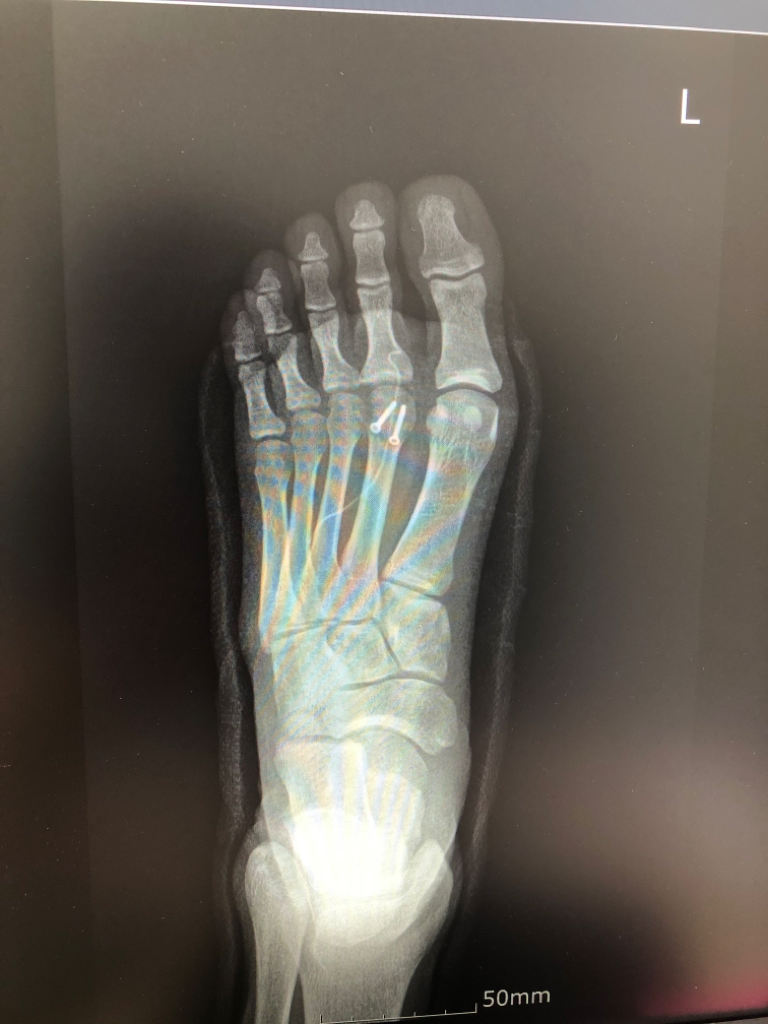

중족골두 핀제거 수술 후 피쏠림 통증?

핀제거 전